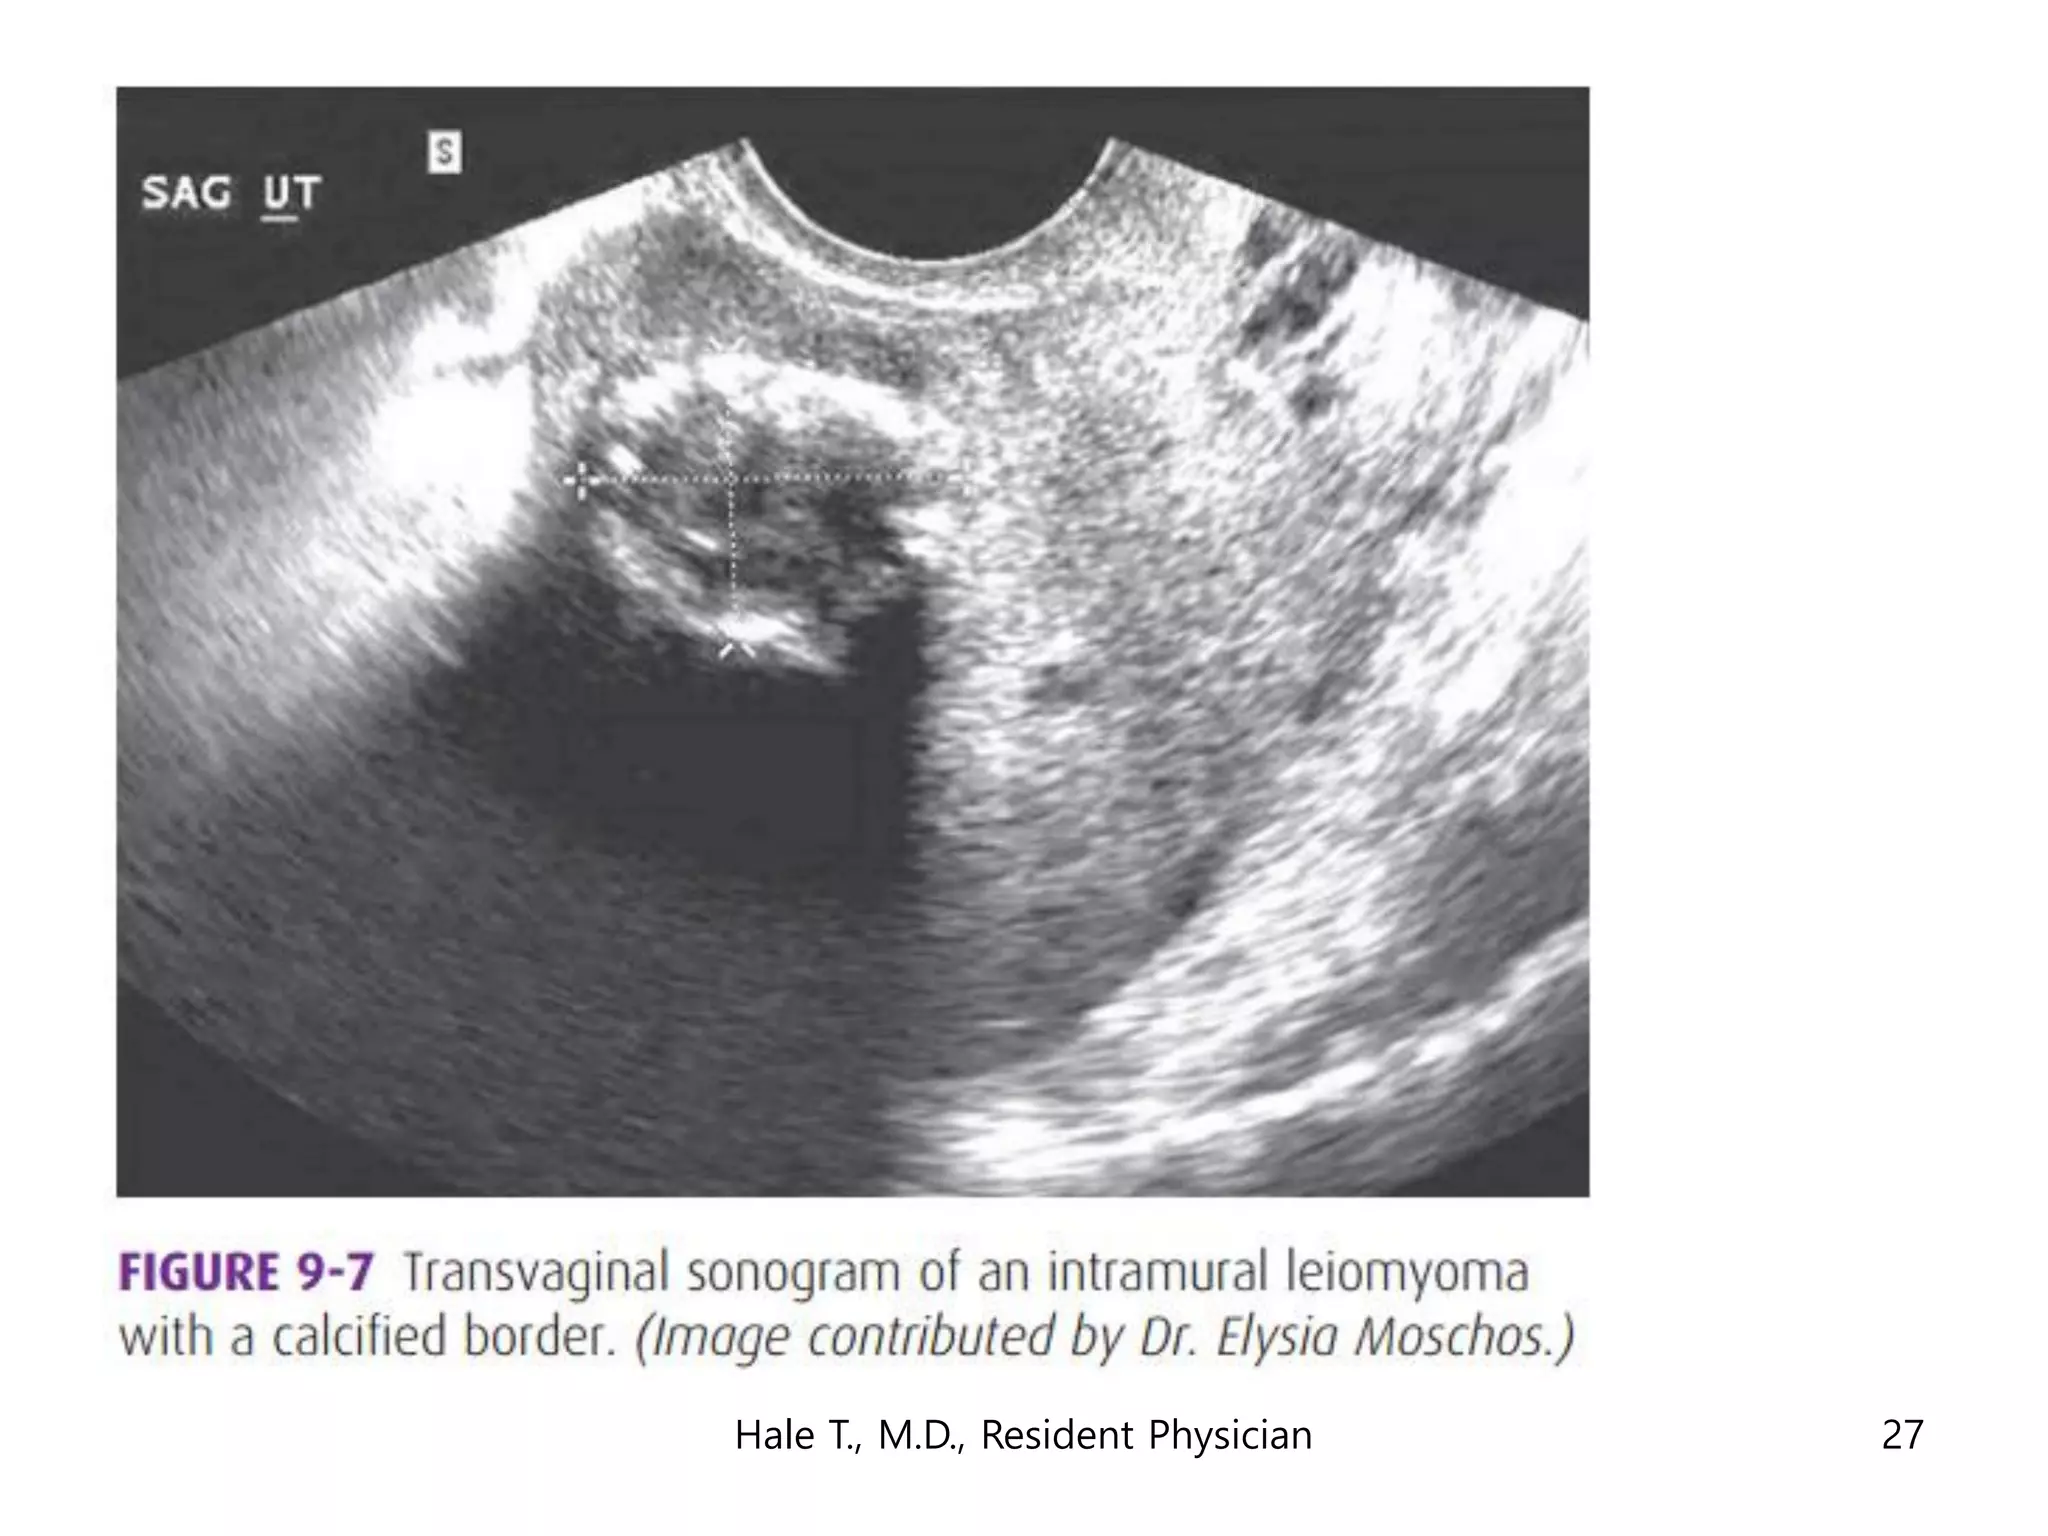

This document discusses myomas (uterine fibroids). It notes that myomas are benign smooth muscle tumors that originate in the uterus and are sensitive to estrogen and progesterone. Symptoms can include bleeding, pain, pressure, and infertility. Diagnosis is usually made through imaging like ultrasound or MRI. Treatment options include observation, drug therapy, uterine artery embolization, or surgical removal of the fibroids. The document also discusses complications that can arise if fibroids are present during pregnancy, such as pain, bleeding, preterm birth, and pregnancy loss.